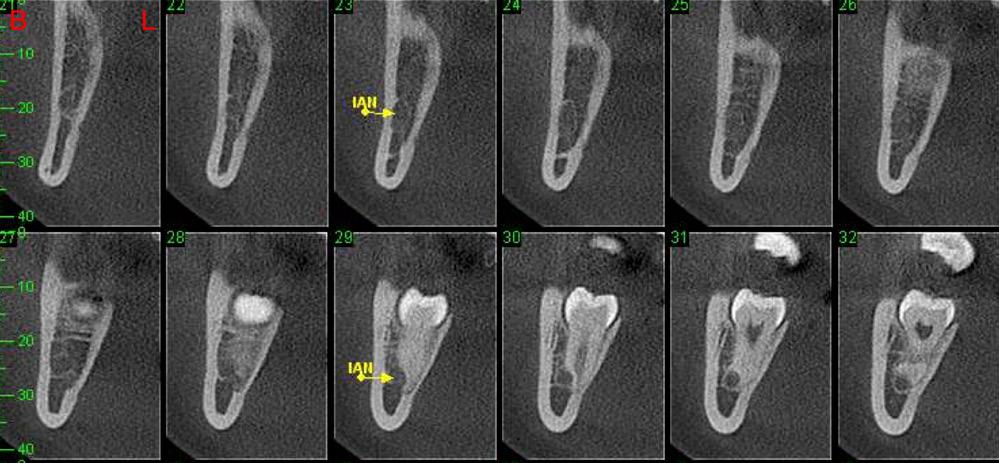

An orthopantomogram (OPG) revealed RL8 and LL8 were mesioangularly impacted and their roots were crossing both upper and lower white lines of the inferior alveolar canal (IAC). LL8 roots showed darkening of root at the level of IAC (Fig 1).

It was decided to request a Cone Beam CT to substantiate findings of the routine OPG in relation to the IAN.

CBCT revealed the following findings:

LL8: IAC was running buccal to roots of LL8 which had 3 roots (Fig 2).

RL8: IAC was seen running between the buccal root which was hooked mesially and lingual roots at its apex, vulnerable to surgical injury (Fig 3).

This case also raises the limitation of the traditional method of imaging with an OPG and shows the importance of CBCT in deciding on the treatment plan. The patient initially visited her dentist in pain with the RL8 and the dentist attempted to remove the tooth to alleviate pain based only on her OPG finding which showed the root apex crossing the upper white line of IAC. Only after referring to a specialist, where CBCT revealed the course of IAC running between the roots of RL8, was the risk of nerve injury avoided.